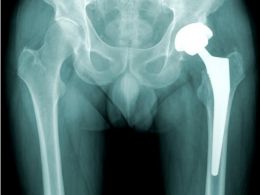

7 formas de prevenir una fractura de cadera en personas mayores

¿Por qué es tan importante prevenir las fracturas de cadera? Esta patología en personas mayores es la causa de ingreso hospitalario en los servicios de traumatología y ortopedia más frecuente en España. Leer +